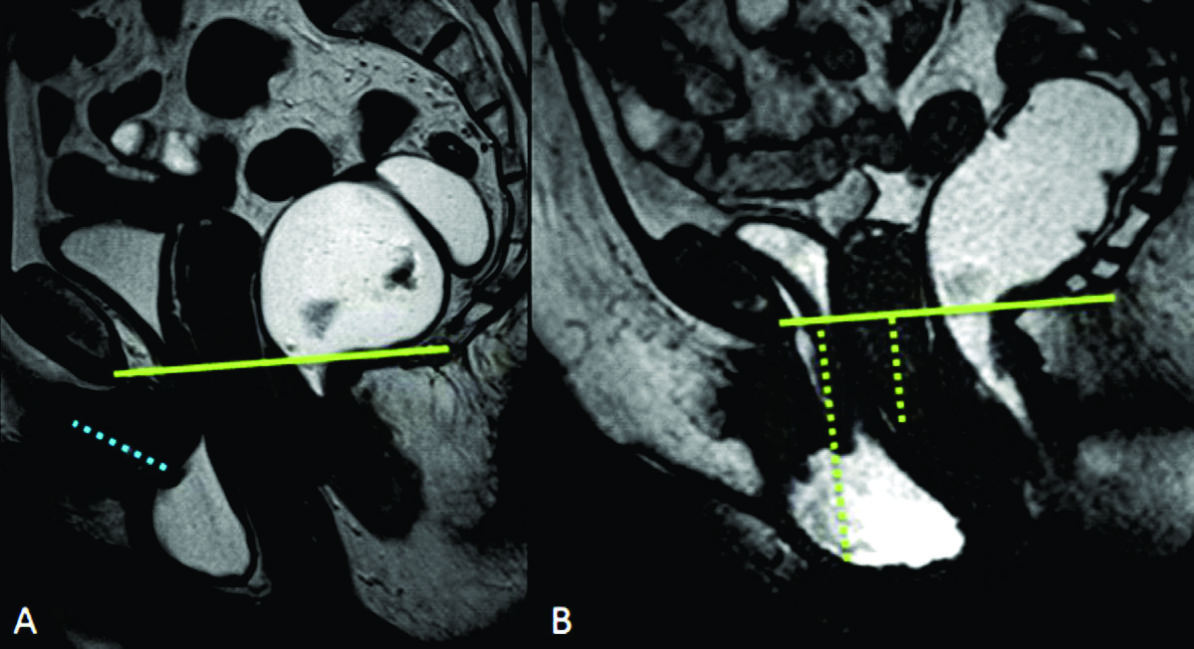

Figura 2

Líneas de referencia. Imagen de la línea media potenciada en T2 en el plano sagital, durante el reposo. Se trazaron la línea PCL (línea continua azul), línea H (línea punteada naranja) y línea M (línea punteada celeste). El músculo puborectal se topografía inmediatamente por detrás de la unión ano-rectal y el plano del elevador es paralelo a la línea PCL.

Figura 3

Ángulos de referencia. Medición del ángulo ano-rectal en una paciente sin patología del piso pélvico. Imagen de la línea media potenciada en T2 en el plano sagital. Durante el reposo el ángulo ano-rectal debe ser entre 108 y 127°. Durante la defecación el ángulo se vuelve más obtuso con una variación de hasta más 20° con respecto al reposo.

La valoración del piso pélvico se hace mediante la valoración morfológica, el sistema HMO y el ángulo ano rectal (Ver figuras 1, 2 y 3) (1)

La valoración morfológica se realiza con secuencias potenciadas en T2 de alta resolución, que permiten un estudio anatómico detallado de los órganos de la pelvis. El sistema HMO constituye un método estandarizado creado para caracterizar y documentar el prolapso y relajación del piso pélvico, que se basa en el trazado de tres líneas fundamentales.

La línea pubococcígea (PCL) se extiende desde el borde inferior del pubis a la última articulación coccígea y representa el nivel de piso pélvico, constituyendo la línea de referencia a partir de la cual se miden los prolapsos, tanto en reposo como en Valsalva.

La línea H se traza desde el borde inferior del pubis hasta la pared posterior del recto a la altura de la unión ano rectal, representando el diámetro anteroposterior del hiato urogenital, con un valor normal menor a 6 cm (Ver figuras 4).

La línea M es perpendicular a la PCL a nivel del sector más posterior de la línea H y representa el descenso del hiato del elevador, con un valor normal menor a 2 cm. El ángulo ano rectal es el ángulo entre el eje central del canal anal y la pared posterior del recto, con un valor normal entre 108º y 127º y una variación de hasta 15º en Valsalva.

Se describe una línea adicional llamada línea media púbica (MPL) que se traza caudalmente siguiendo el eje mayor de la sínfisis del pubis. Esta línea corresponde al nivel del himen vaginal, el cual es utilizado históricamente como punto de referencia para la valoración clínica. 12-13